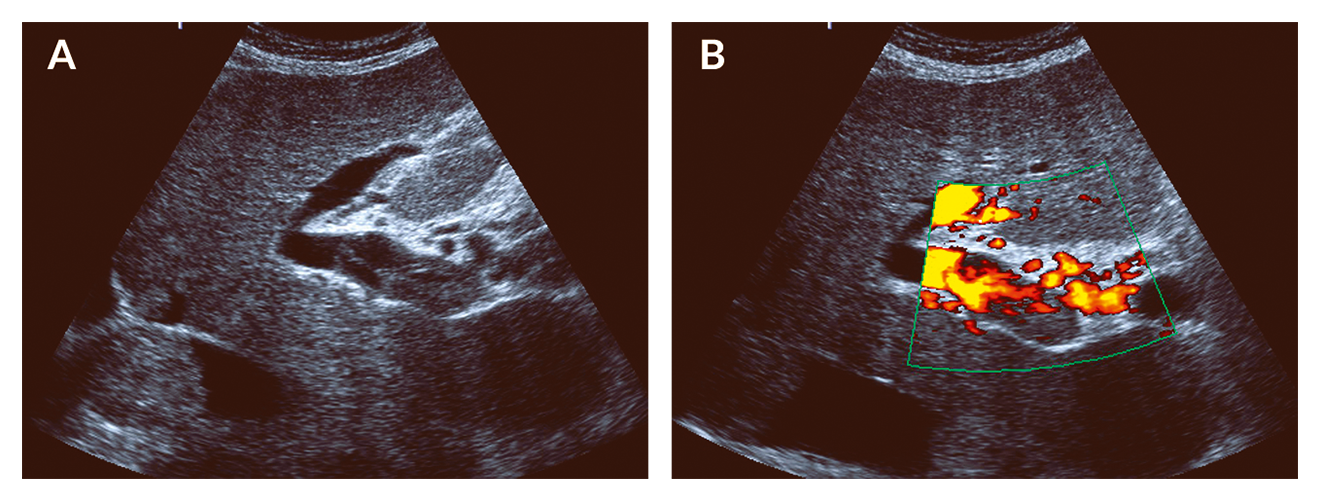

Imaging techniques are used to confirm hepatomegaly or ascites and will help to rule out differential diagnoses such as biliary obstruction. A more specific sign is the finding of hepatic inflow blockage with reduced or reversed portal flow in colour Doppler ultrasound (Figure 1). In addition, attenuation of hepatic venous flow or gallbladder wall edema may be detected. Some authors suggest the use of composite ultrasound imaging scores (Lassau 2002). Though less specific, CT imaging (i.e. heterogeneous hypoattenuation and patchy enhancement in the portal venous or equilibrium phase) may be suggestive for SOS (Yang 2018).

Figure 1. Doppler ultrasound in sinusoidal obstruction syndrome. Exemplary case showing undulating portal venous flow in a jaundiced patient after HSCTx